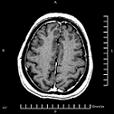

ER, servono neurologi d'urgenzaIl tasso di mortalità a 30 giorni è pari al 50% per ematomi intracerebrali, al 29% per traumi cranici, al 20% per casi di epilessia; inoltre, il 50% delle emorragie subaracnoidee sarebbero fatali. Per questo – sostiene Kathlyn Stone su Lancet – anche la presenza di neurologi nelle “Emergency Room (ER)” risulta decisiva nel salvare vite umane (Stone K, When seconds count: tackling neurological emergencies, Lancet Neurology, August 2009).